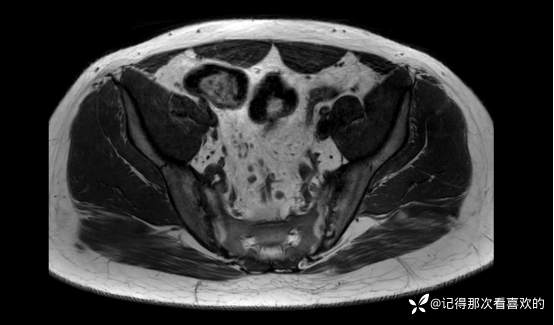

06-05 骶髂关节MRI平扫:1、双侧骶髂关节改变,符合为强直性脊柱炎所致。请结合临床实验室检查结果。2、左髋关节少量积液。请结合临床及其他检查,随诊。